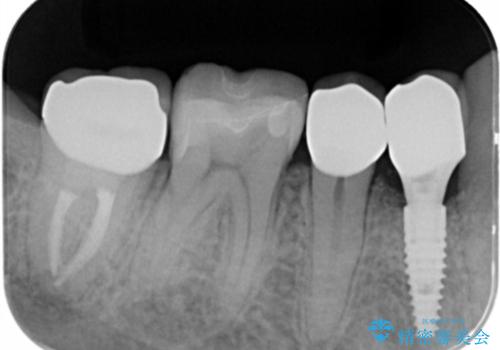

- 過去、多数の部位の虫歯治療を受けこれまで再発を繰り返してきたことから「徹底的な虫歯治療を受けたい。」と希望され来院されました。

虫歯の大きさから保存できなかった歯はインプラント治療を行い、その他の歯は虫歯のステージに合わせて根管治療、セラミックインレー、 セラミッククラウンを精密に行うことで長期的な予後を期待できる状態へと治療を進めます。